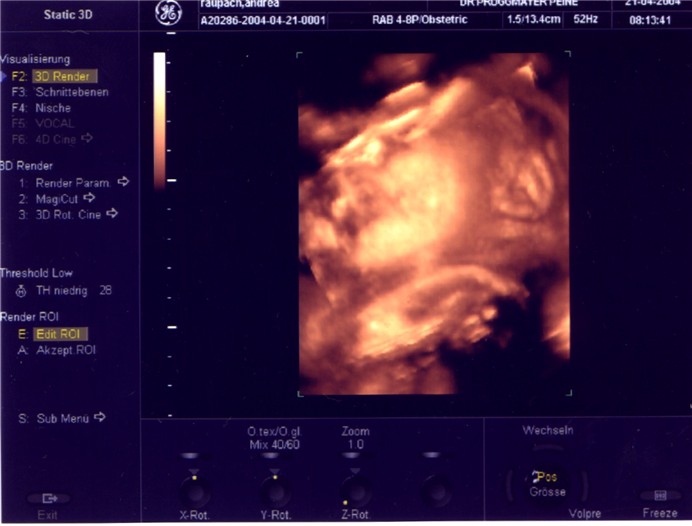

hatte heute endlich meinen lang ersehnten 3D Bild Termin von unserem kieselchen..

Leider war er nicht ganz erfolgreich, sie liegt ziemlich versteckt und kuschelt mit der Plazenta als wäre es ihr Kopfkissen. :-o Aber immerhin eine süße kleine rechte Handinnenfläche haben wir erhaschen können und ihr rechtes kleines Öhrchen (ganz der Papa - habe ich sofort gesehen!!

sie liegt ziemlich versteckt und kuschelt mit der Plazenta als wäre es ihr Kopfkissen. :-o Aber immerhin eine süße kleine rechte Handinnenfläche haben wir erhaschen können und ihr rechtes kleines Öhrchen (ganz der Papa - habe ich sofort gesehen!!  ) und man kann nur die Anrissen von Augen, Nase und Mund erahnen. und eine Hand liegt so quer über ihren Hals..Aber in zwei Wochen sehen wir noch mal "nach".. obwohl ich nicht wirklich daran glaube das sie dann besser liegen wird. :-?

) und man kann nur die Anrissen von Augen, Nase und Mund erahnen. und eine Hand liegt so quer über ihren Hals..Aber in zwei Wochen sehen wir noch mal "nach".. obwohl ich nicht wirklich daran glaube das sie dann besser liegen wird. :-?

Dann müssen wir uns halt vom "Rest" überraschen lassen und warten natürlich voller Neugier ..